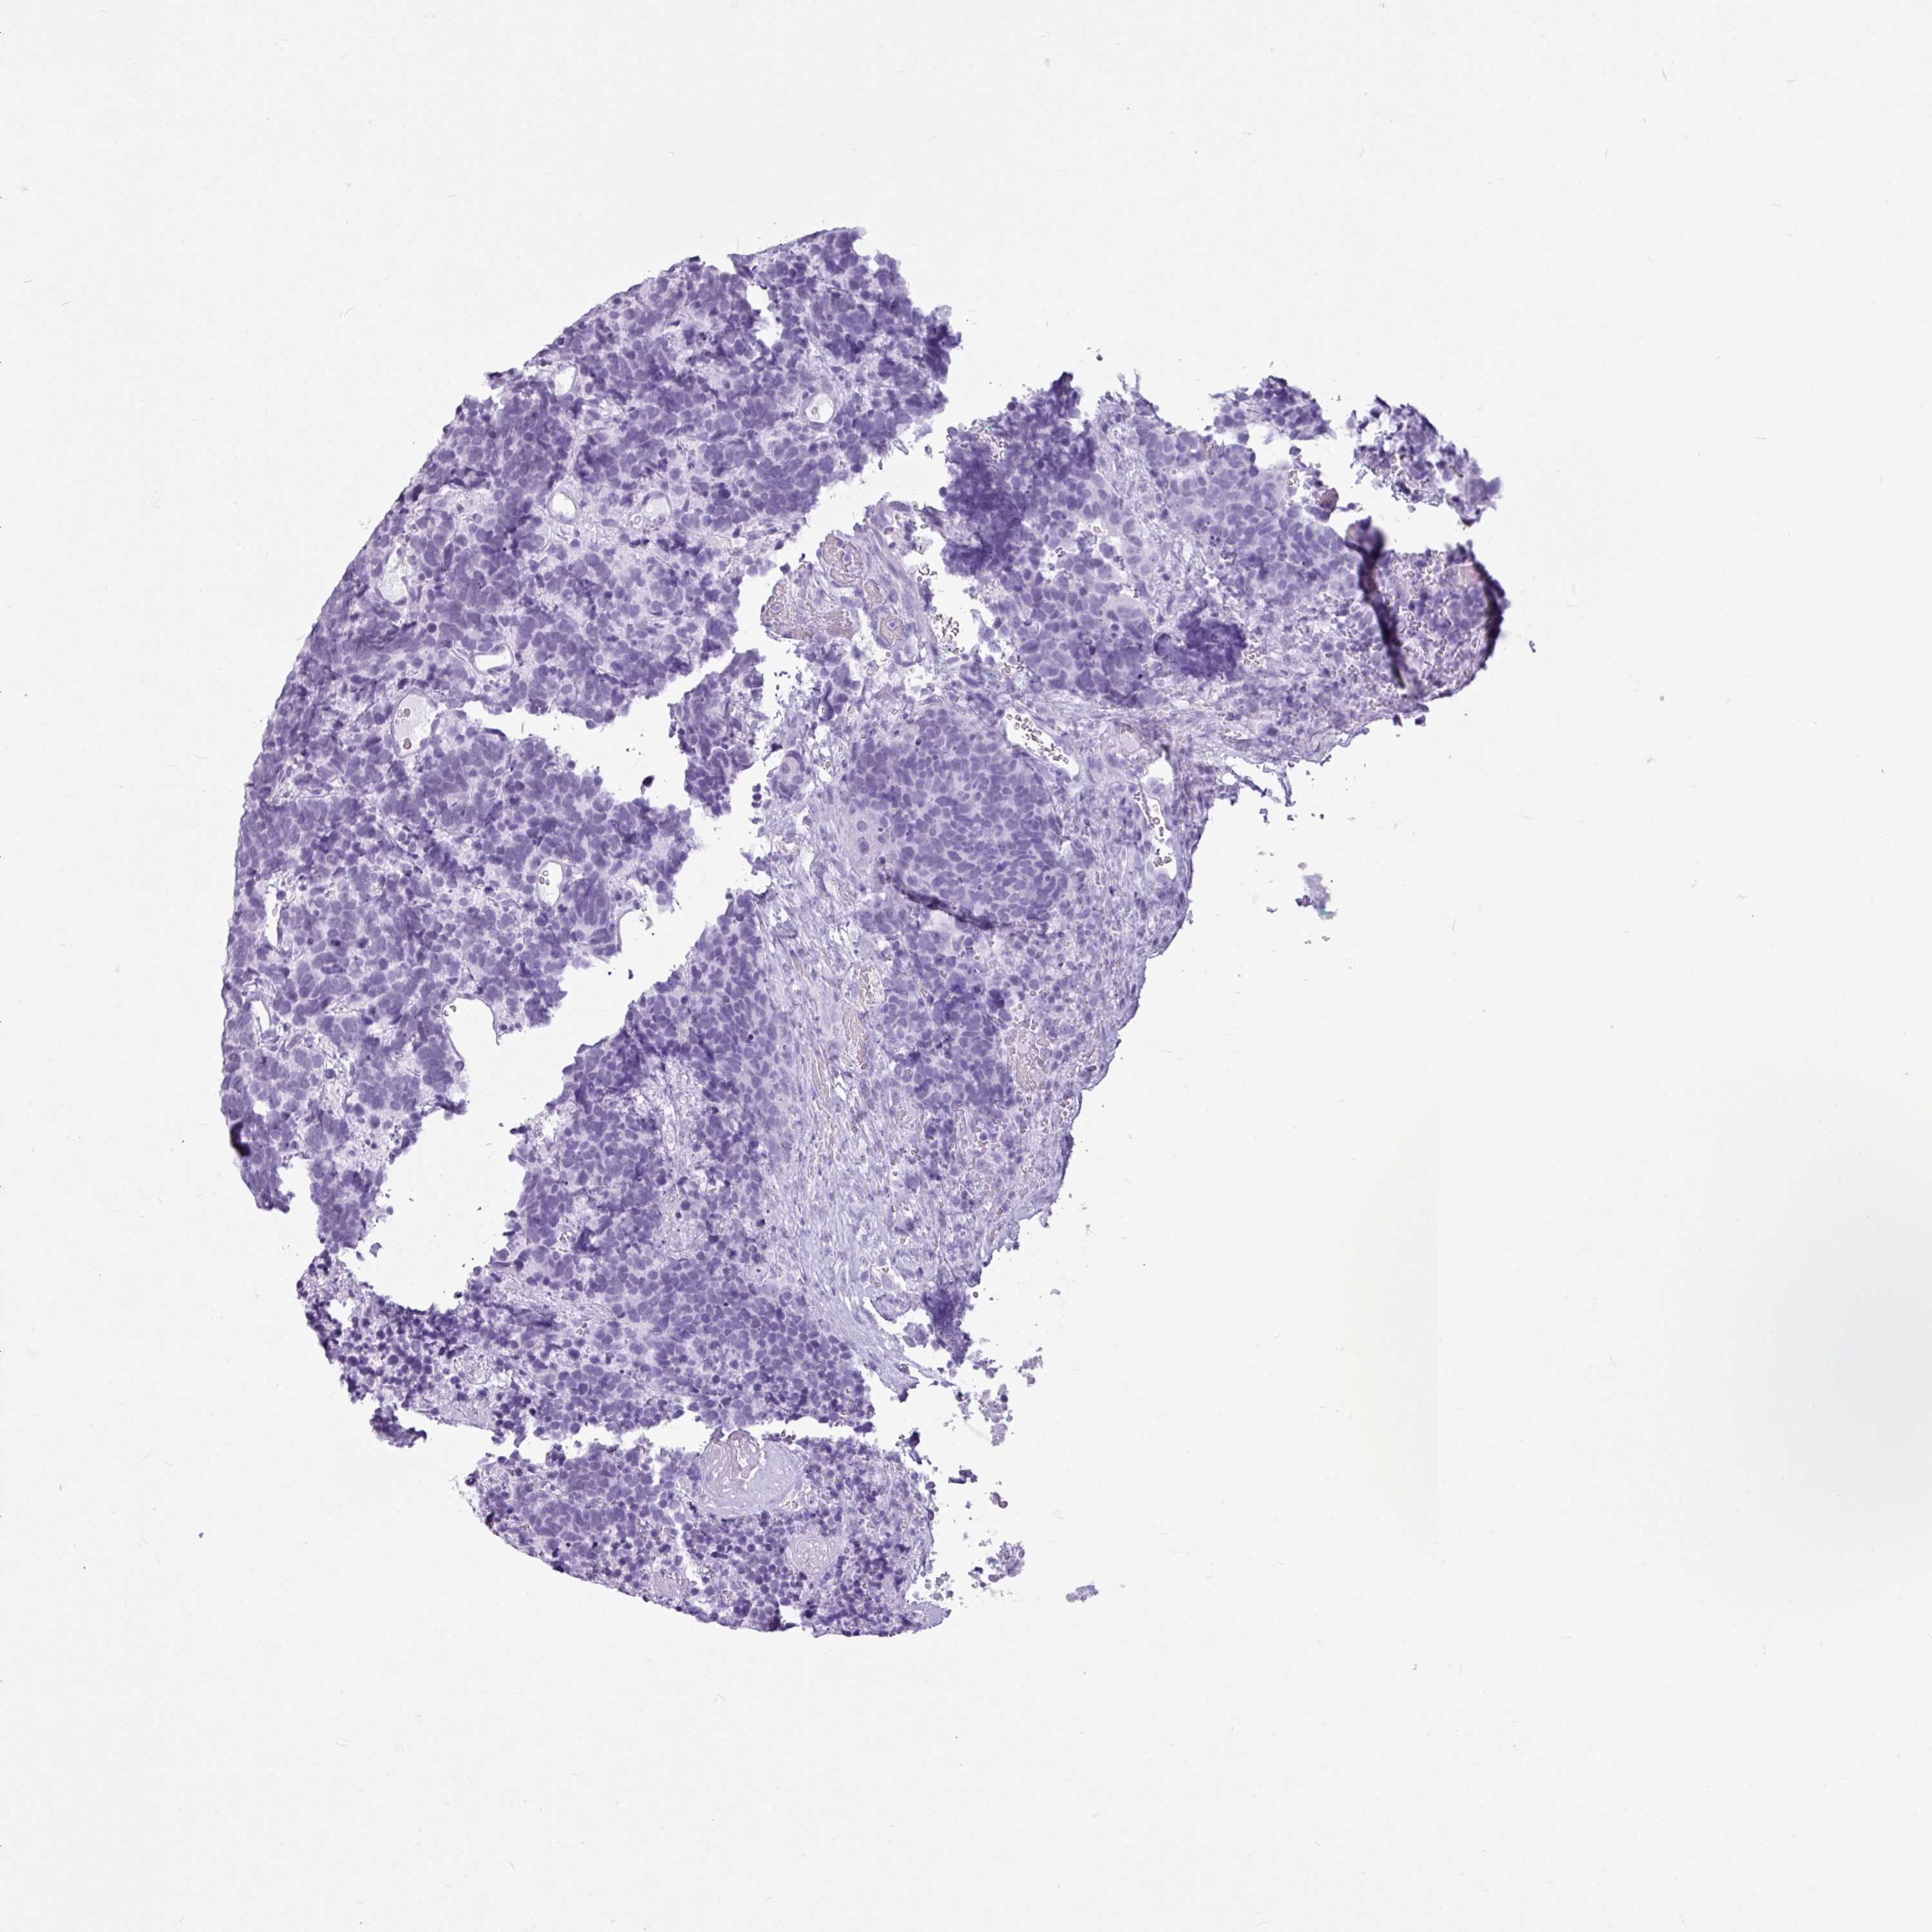

AMY1C